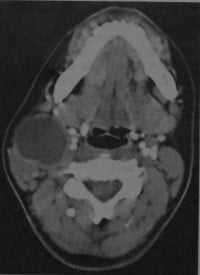

КТ шеи. Слева от средней линии в сонном пространстве кистозное образование (кистозно измененный лимфоузел).

- Кистозное образование (10-25 HU) латеральнее нервно-сосудистого пучка (до 10 см в диаметре)

- Смещает поднижнечелюстную железу кпереди и медиально, грудино-ключично-сосцевидную мышцу - кзади и латерально

- Часто расположена рядом с углом нижней челюсти, иногда в окологлоточном пространстве или кпереди от нервно-сосудистого пучка

- Кровоизлияния в полость кисты и перегородки в ней встречаются редко

- Утолщение стенки и ее усиление после введения контраста наблюдается только в случае инфицирования кисты.

Инфицированная бранхиогенная киста. КТ с контрастированием: киста на уровне правого угла нижней челюсти. Наблюдается утолщение и усиление стенки кисты, а также снижение плотности в центре образования. Грудино-ключично- сосцевидная мышца смещена кзади и лате рально, нервно-сосудистый пучок - медиально.